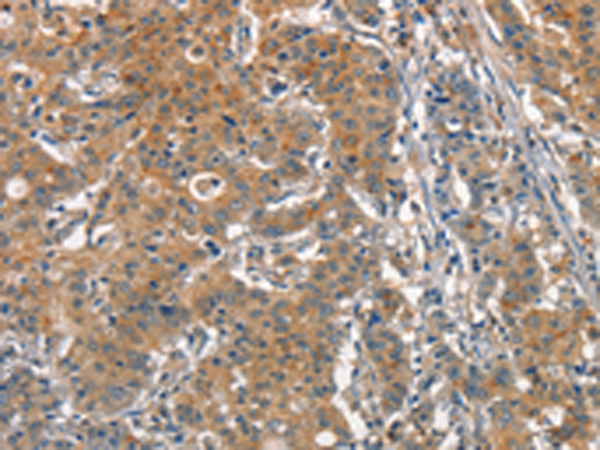

分类: 科研抗体货号: P11270别名: 2ADUB, 2A-DUB, RP4-592A1.1应用: WB,IHC反应种属: Human, Mouse